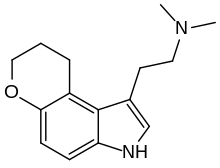

| CP-132,484 | artificial | 1-methyl-4,5-(OCH2CH2CH2) | H | H | 1-(2-aminoethyl)-3-methyl-8,9-dihydropyrano(3,2-e)indole | 143508-76-3 |

| 4,5-DHP-DMT | artificial | 4,5-(OCH2CH2CH2) | CH3 | CH3 | 1-(2-dimethylaminoethyl)-8,9-dihydropyrano[3,2-e]indole | 135360-97-3 |